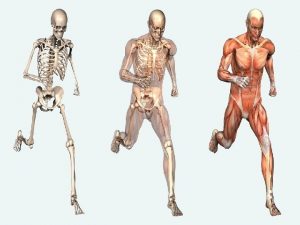

Skeletal System (1 of 2) • Skeleton: rigid supporting structure of the body – All bones have same basic structure • Cortex: outer layer of compact bone, the cortex • Trabeculae: inner spongy layer arranged in a loose meshed lattice of thin strands • Bone marrow: spaces between trabeculae consist of fat and blood-forming tissue • Bone: specialized type of connective tissue – Composed of a dense connective tissue framework impregnated with calcium phosphate salts – Continually broken down and reformed

Skeletal System (2 of 2) • Types of cells in bone – Osteoblasts – Osteocytes – Osteoclasts • Strength and thickness of bones depend on activity • Bones of skeleton are connected by joints • Types of joints – Fibrous joint – Cartilaginous joint – Synovial joint

Skeletal Muscle (1 of 3) • Muscle contraction – Myofilaments slide together – Myoneural junction: communication between nerve and muscle – Nerve stimulation releases acetylcholine that interacts with receptors on surface of muscle fibers andinitiates contraction • Normal structural and functional integrity depends on – Intact nerve supply – Normal transmission of impulses across myoneural junction – Normal metabolic processes within muscle cell